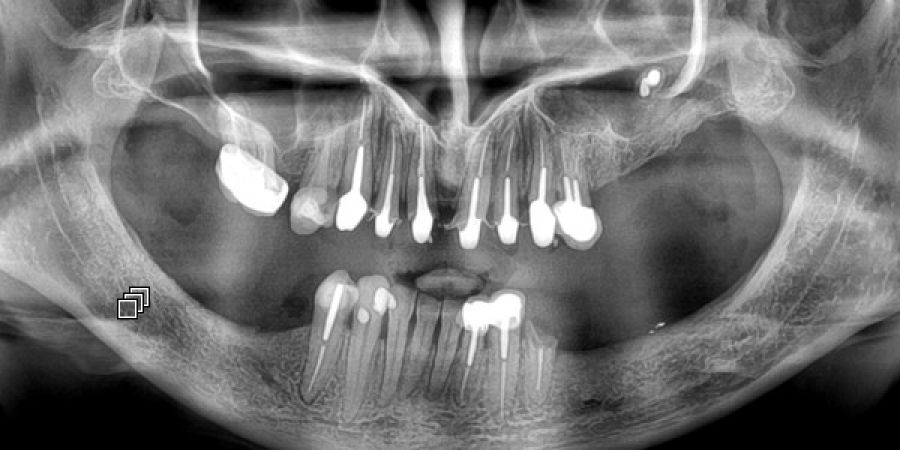

Fréquemment demandé et utilisé pour les soins dentaires, l'imagerie dentaire est aussi souvent utilisée pour la recherche de pathologies sinusiennes

Le panoramique dentaire est un appareil de radiographie qui effectue une rotation autour de votre tête afin de dérouler toute l'arcade dentaire sur un seul plan.

L'appareil tourne autour de votre tête pour réaliser l'acquisition . La technique est celle de la radio et utilise les rayons X